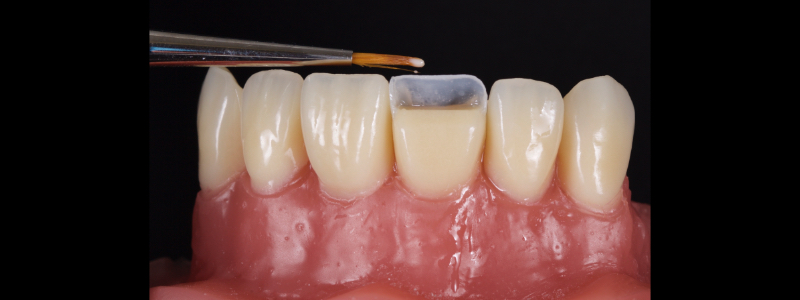

To achieve this, the achromatic enamel mass is first placed on a PVS Putty stent made from a diagnostic wax-up with a flat plastic (see the first article in this series for more detail). The enamel mass is thinned with a flat plastic in combination with a multipurpose condenser, a #3 brush (i.e., GC, Cosmedent, Tokuyama), and some modeling resin (Fig. 7).

A modeling resin is a liquid resin that does not contain HEMA — examples include modeling resin (Bisco), Brush and Sculpt (Cosmedent), and Signum (Kulzer). The unpolymerized resin is then carried in the stent to the tooth and adapted to the palatal margin with a #3 brush (Fig. 8).